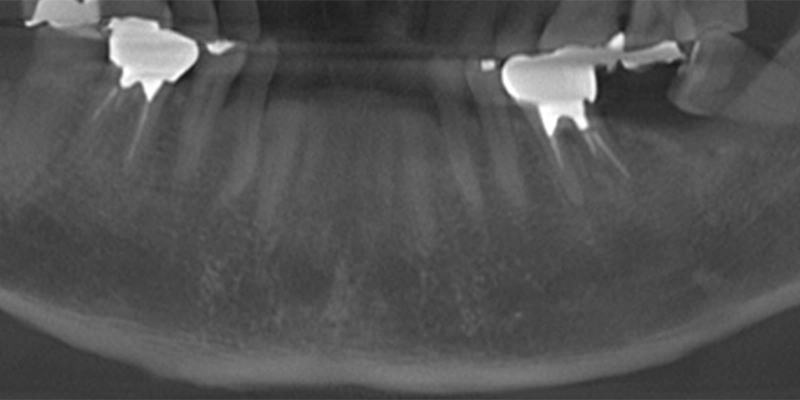

| 主訴 | 噛むと痛い |

|---|---|

| 診断名 | ⻭根破折 |

| 年齢・性別 | 70歳・⼥性 |

| 治療期間・回数 | 8ヶ⽉・6回 |

| 治療方法 | サイナスリフト、インプラント |

| 費用 | 975,700円 |

| 治療上のリスク |

|